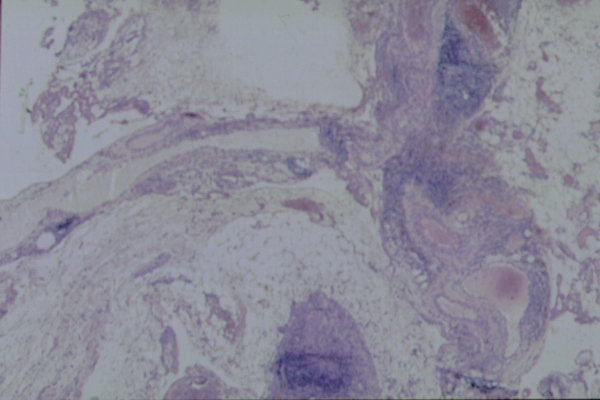

fig. 5

Figura 5. Proliferación de tejido fibroso con infiltrado inflamatorio mixto ocasionalmente perivascular. Presencia de agregados linfoides